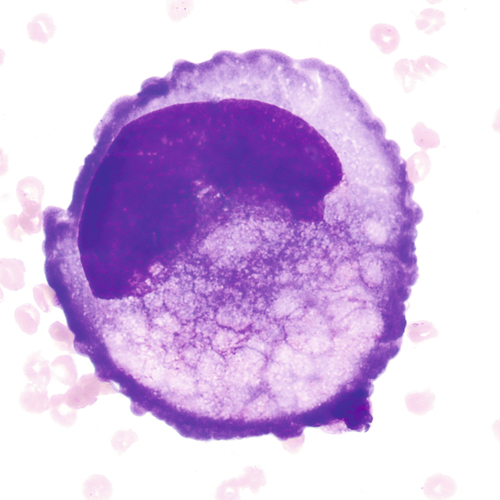

Large cells with eccentric nuclei and vacuolated cytoplasm may be present in all body fluids. They may be seen with or without inclusions, such as RBCs, siderotic granules, or lipids.

Round to oval cell with eccentric nuclei, dark blue cytoplasm, perinuclear hof 8 to 29 μm in diameter